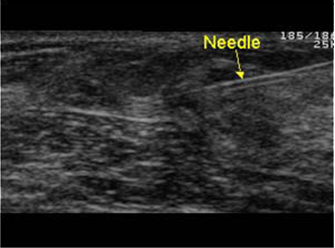

ε) Για να πραγματοποιήσουμε επεμβατική πράξη, όπου καθοδηγούμε τη βελόνα με τους υπερήχους για βιοψία συμπαγούς μορφώματος (εικόνα 4) ή εκκένωση κύστης (εικόνες 5,6) ή τοποθέτηση συρμάτινου οδηγού σε ογκίδιο για την ακριβή εξαίρεσή του χειρουργικά.

(Εικόνα 4)

(Εικόνα 5)

(Εικόνα 6)